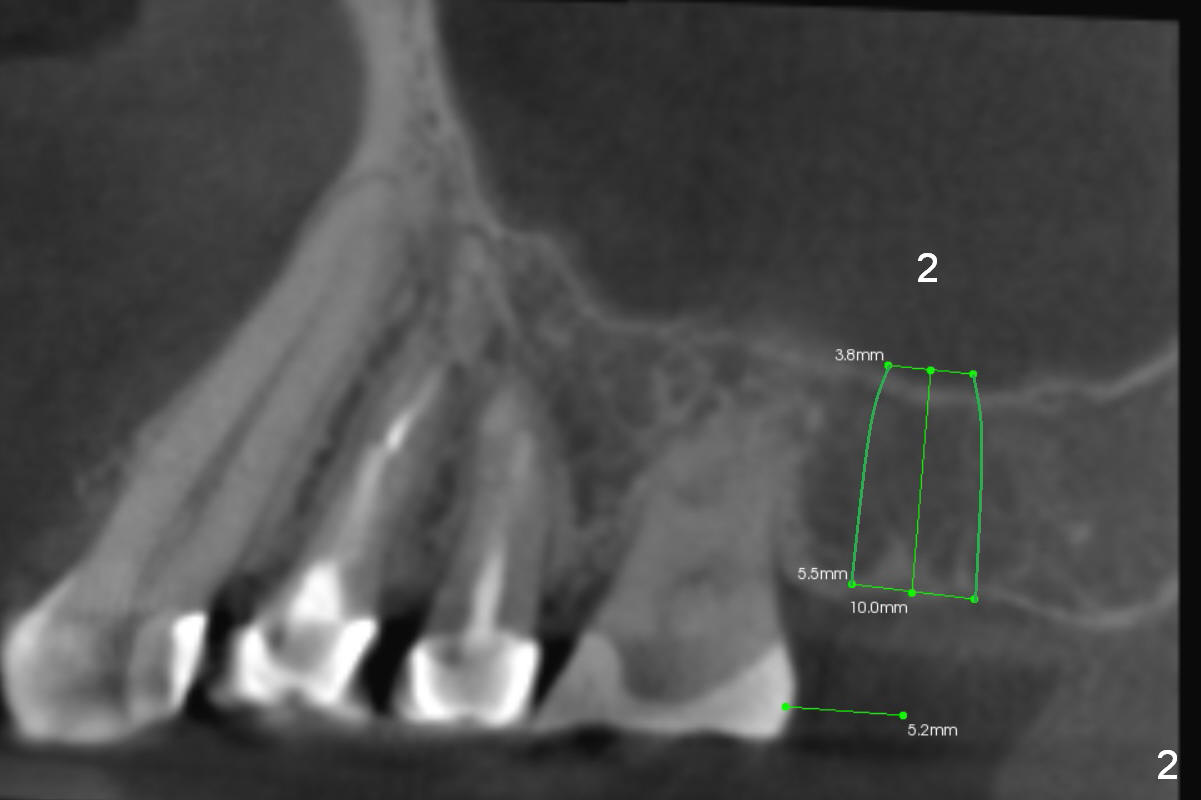

To handle the 2nd challenge, start bone expansion with #15 and osteotomes (from 8 to 11 mm). Set implant spacer at 4 mm (Fig.2). Prepare allograft (.5-1 mm) and Osteogen (4:1 ratio) for sinus lift. Place 8 mm stopper on the larger condenser from Sinus Master Kit.